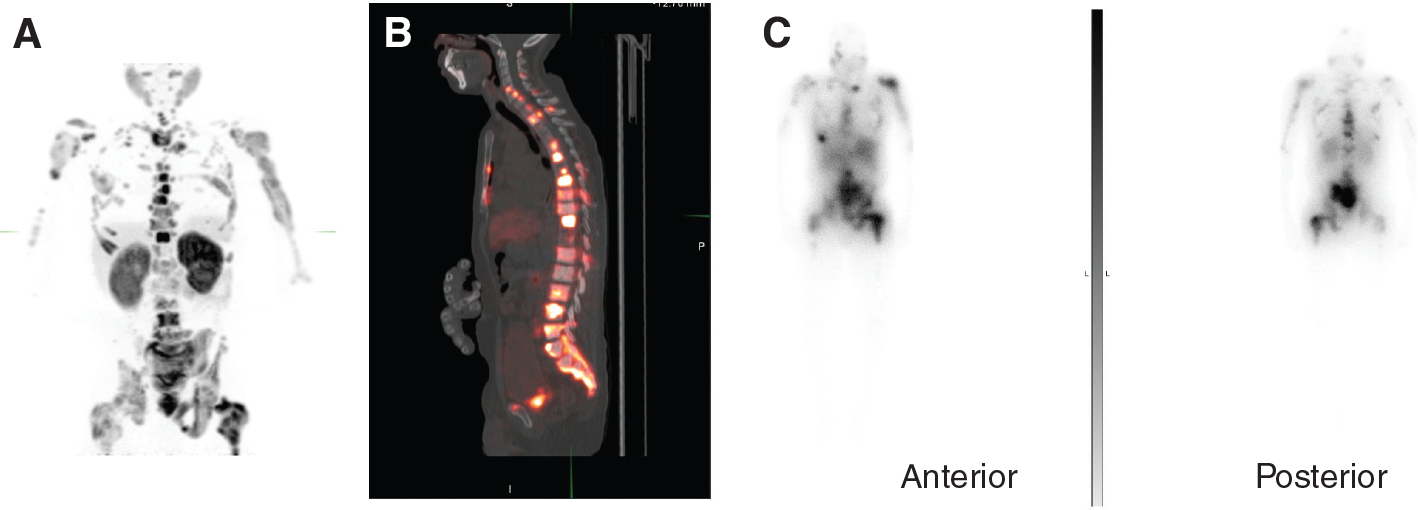

Fig 2

Figure 2. An 82-year-old man with metastatic prostate cancer, but with limited PSMA expression of disease, ineligible for 177Lu- PSMA-617 RLT. A. Maximum intensity projection image of 18F-PyL PSMA PET/CT; B. axial CT image of the chest demonstrating one osteoblastic rib lesion and mild uptake in the sternal body and a right-sided rib; C. axial PSMA PET image demonstrating uptake related to the osteoblastic rib lesion and mild uptake in the sternal body and a right-sided rib; D. fused PET/CT images of B and C; E. axial CT image demonstrating an osteoblastic right iliac bone lesion; F. PSMA PET image demonstrating limited uptake associated with the osteoblastic lesion; G. fused images of E and F.